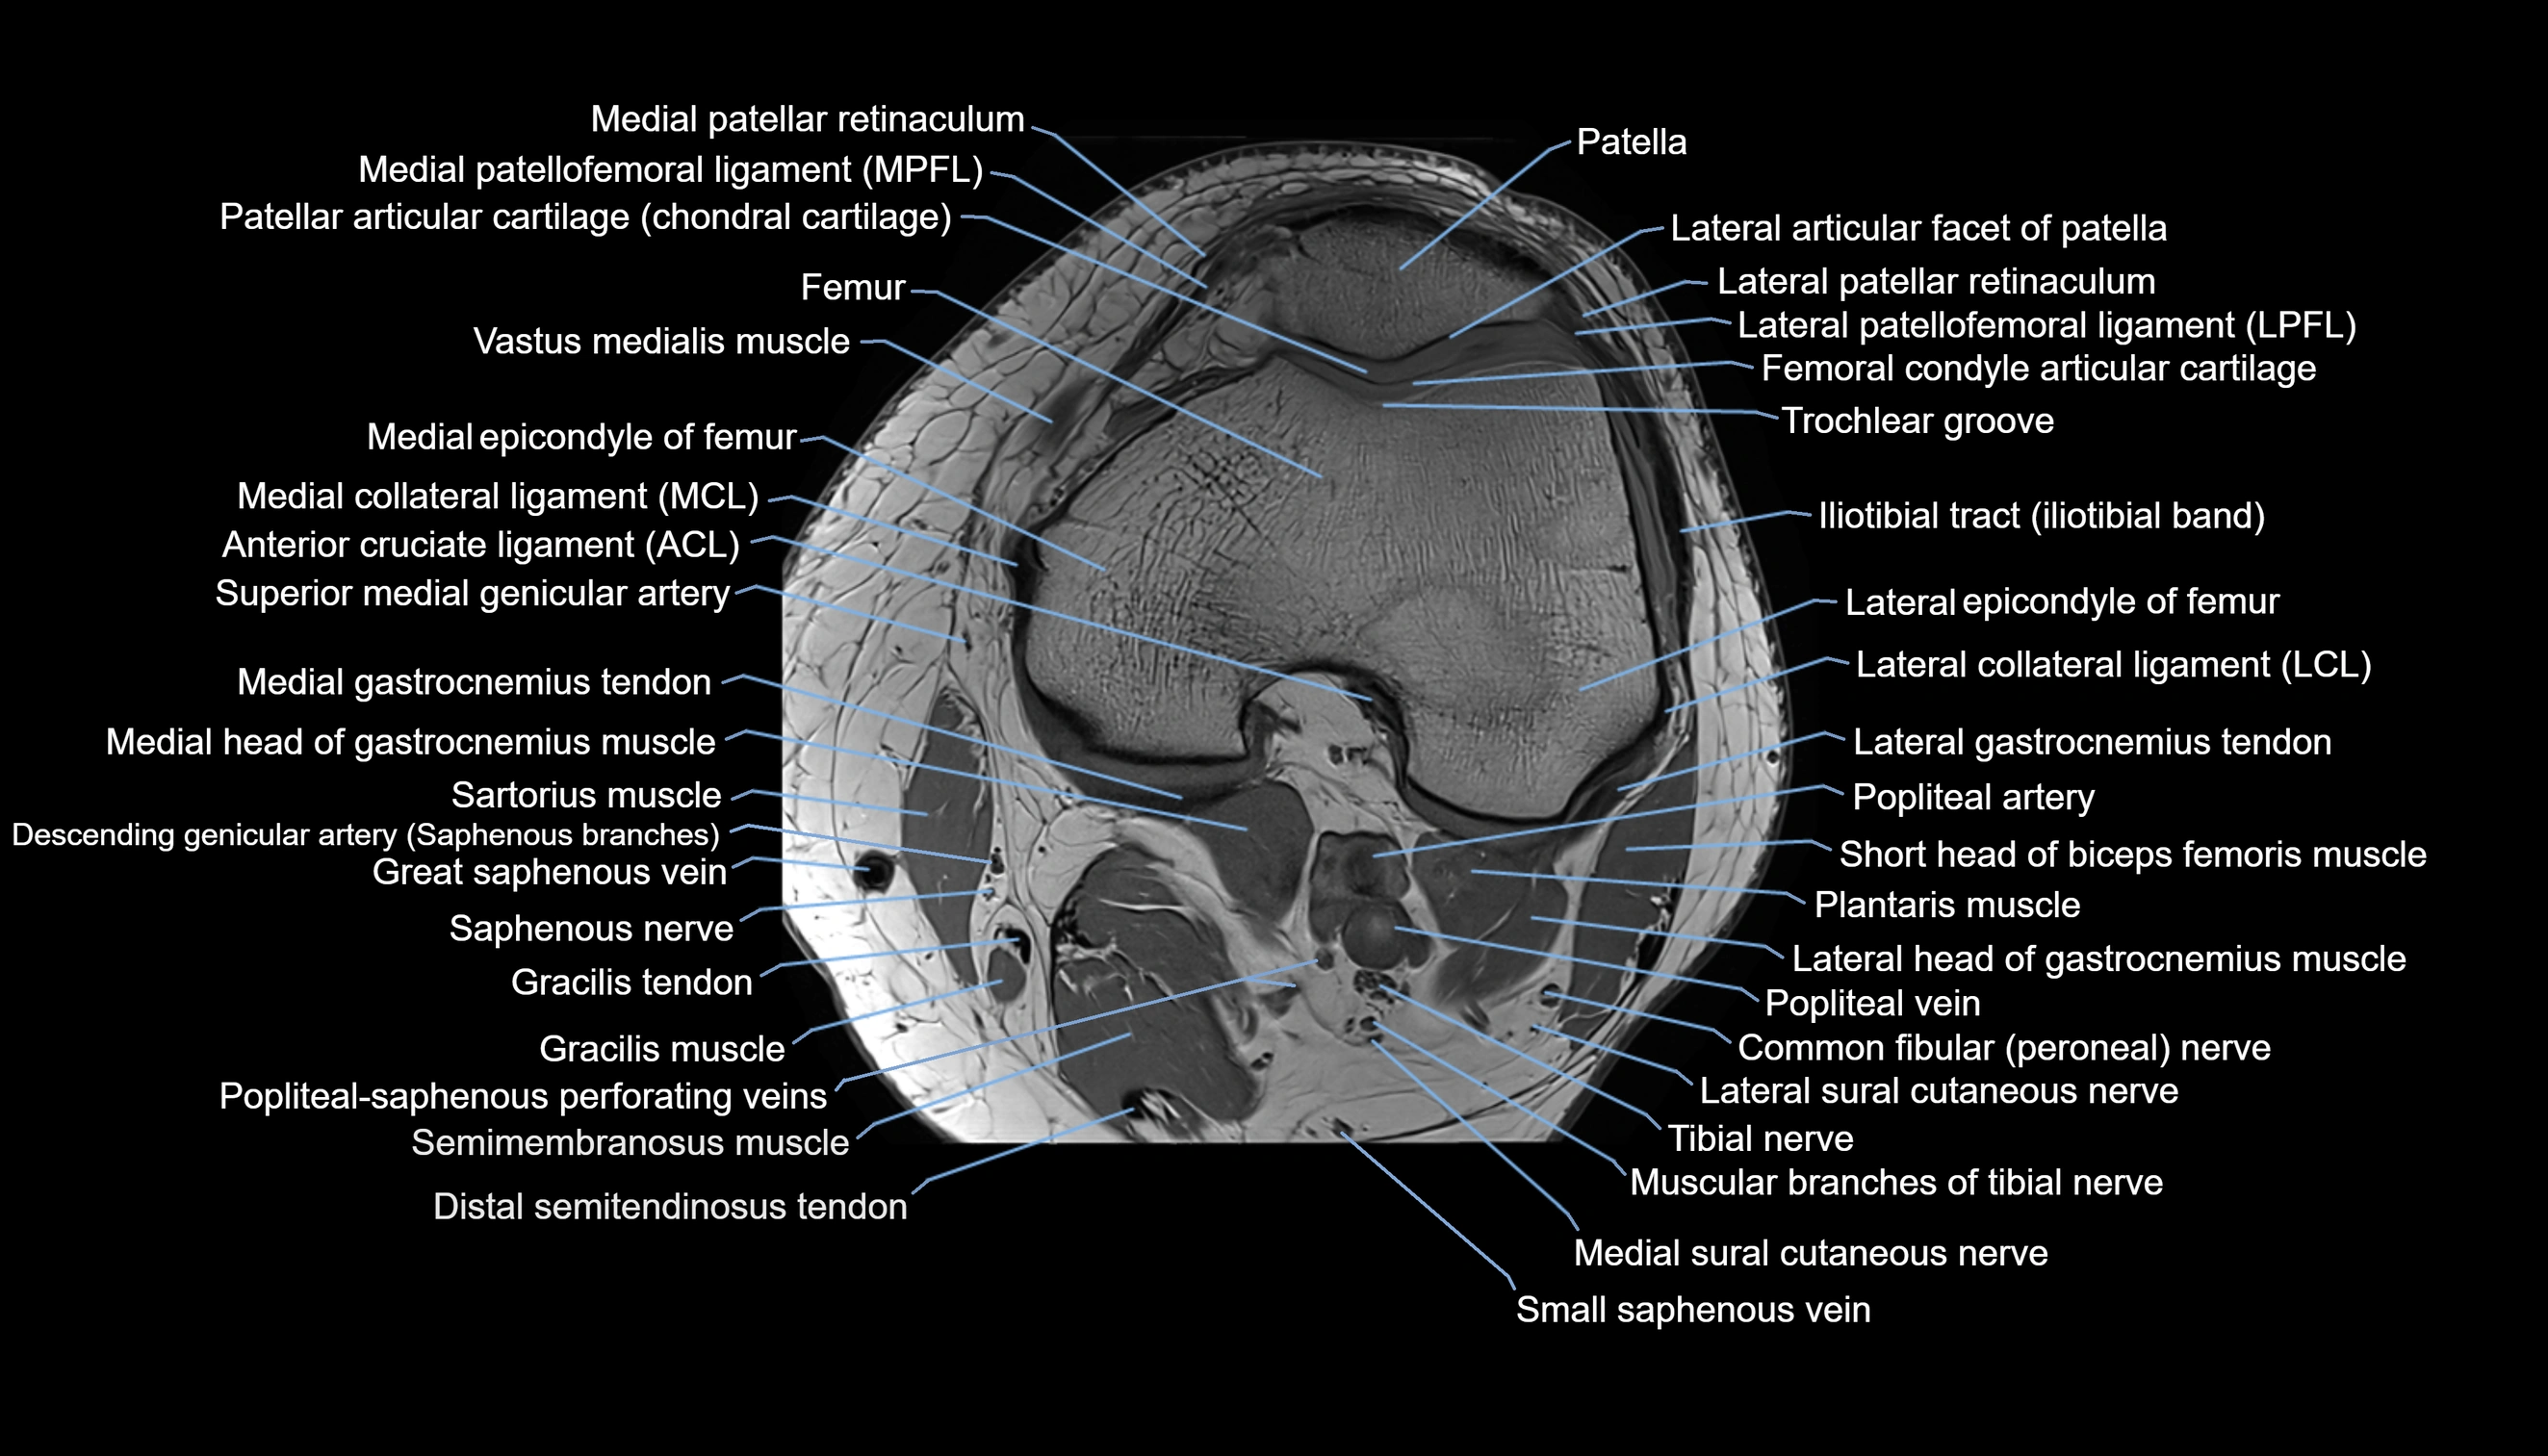

- Knee Joint

- Lateral articular facet of patella

- Lateral patellar retinaculum

- Lateral patellofemoral ligament

- Medial collateral ligament

- Medial epicondyle of femur

- Medial gastrocnemius tendon

- Medial head of gastrocnemius muscle

- Medial patellar retinaculum

- Medial patellofemoral ligament

- Muscular branches of tibial nerve

- Patella

- Patellar articular cartilage

- Popliteal artery

- Popliteal vein

- Popliteal–Saphenous perforating veins

- Saphenous nerve

- Sartorius muscle

- Semimembranosus muscle

- Small saphenous vein

- Superior medial genicular artery

- Tibial nerve

- Trochlear groove

- Vastus medialis muscle

- great saphenous vein